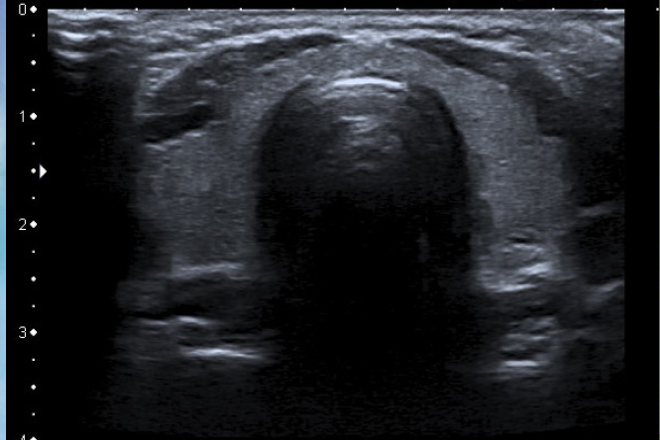

Valoración ecográfica de la patología ovárica

El ultrasonido ha sido una herramienta útil en el diagnostico temprano de multiples patologías uterinas, las más comunes pueden clasificarse en 3 grupos: Patología del miometrio Patología endometrial Otras patologías. Dentro de las patologías miometriales se encuentran los MIOMAS, sus manifestaciones clínicas se relacionan en